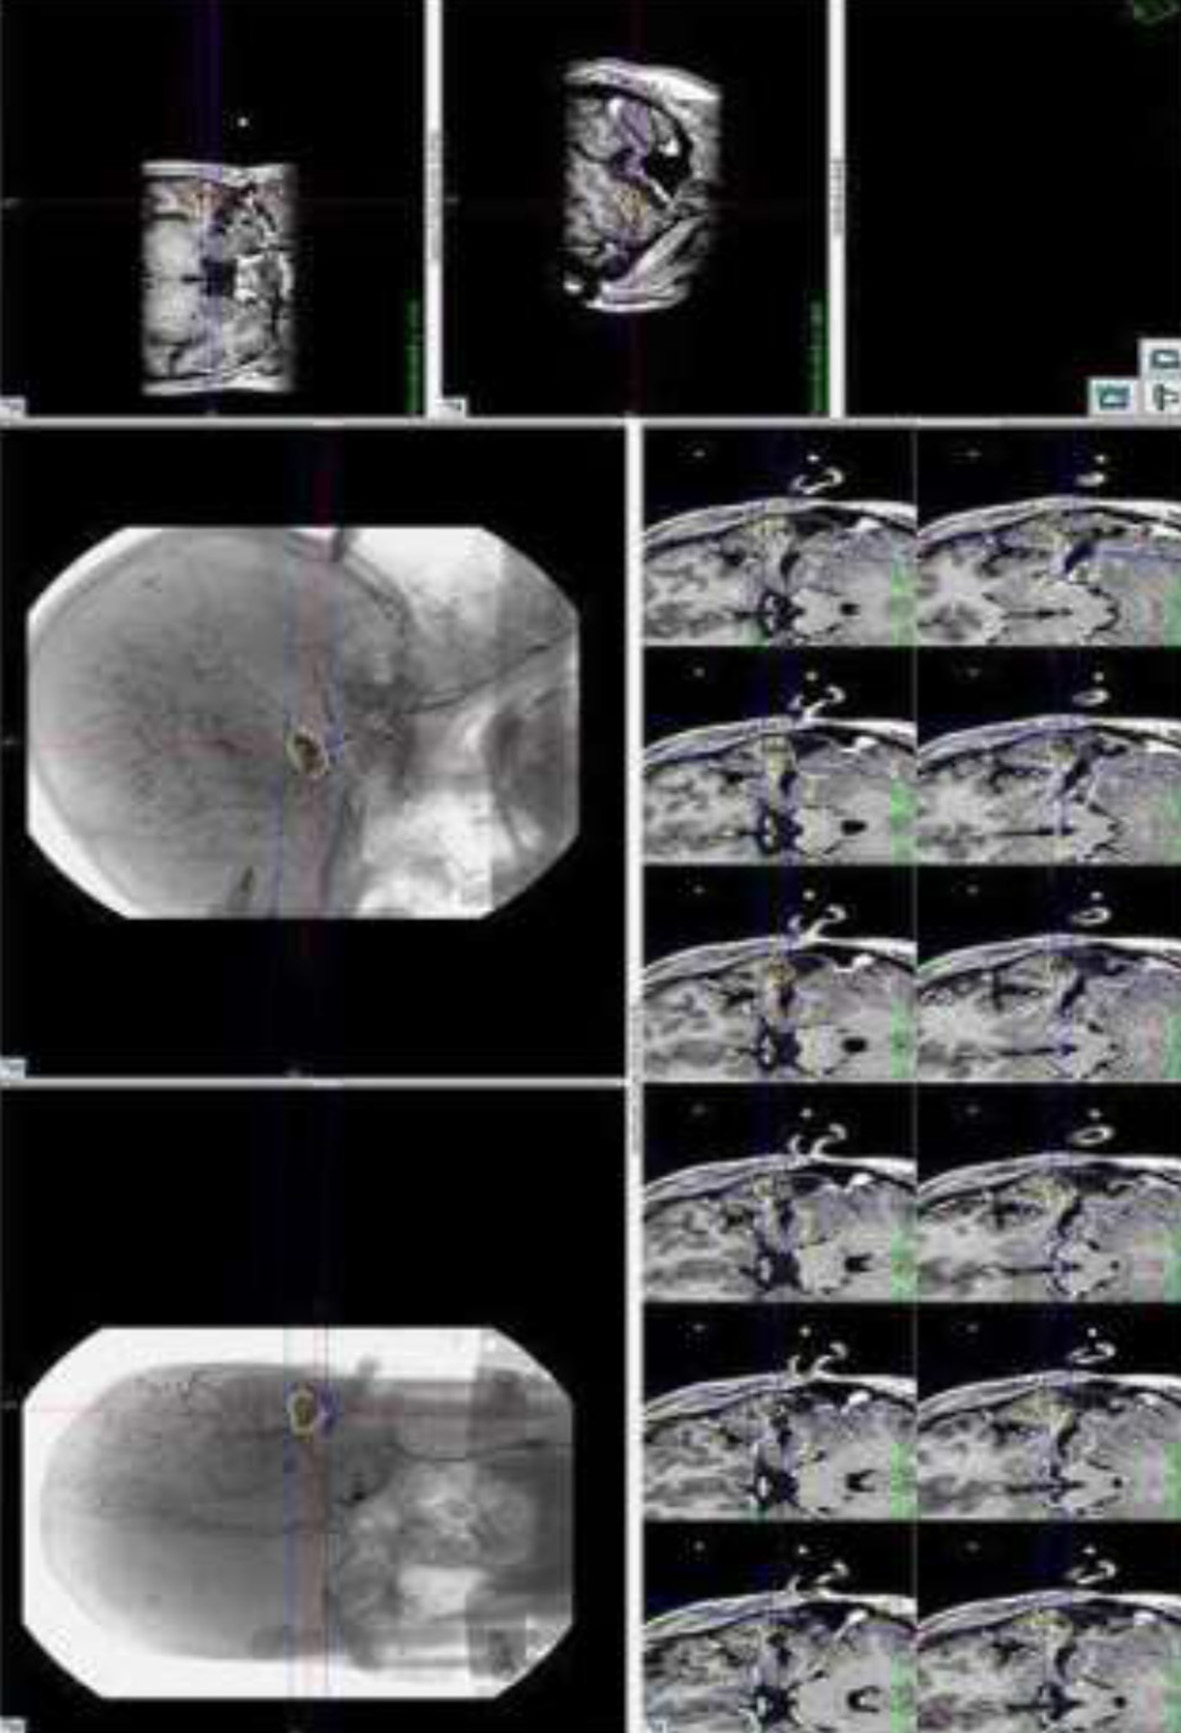

Fig. 2, 3, 4, 5 are the representative images of the patients, showing the AVM, its localisation and planning for purely descriptive purpose only.

Fig. 5. Representative image showing I Gamma Knife Planning for Left temporal AVM Management